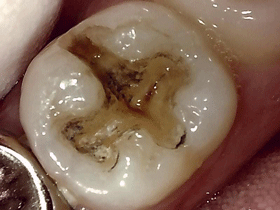

当院では取り残ししない様、肉眼的・触知的確認だけでなく虫歯検知液を使ってチェックします

またできる限り虫歯の状態も口腔内カメラで撮影した画像をお見せして治療します

う蝕検知液 光学式う蝕検出器

症 例